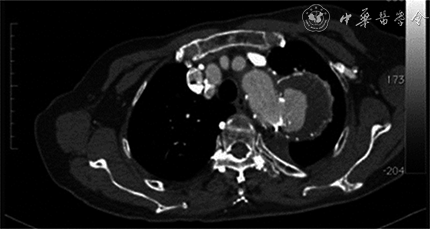

可以说,国外对主动脉夹层或夹层动脉瘤可以施行腔内治疗的了解和广泛应用基本在我国之后,但外人一旦觉醒,其大支架仍然迅速后来居上,目前国内市场中进口者比比皆是。Relay型支架可在升主动脉、主动脉弓中自如操作,我有幸为该支架完成国内首例在患者中的应用。自1999至2004年我们完成137例以主动脉夹层为主的大动脉病变的腔内治疗。到2010年,据不完全统计,北京大学人民医院、首都医科大学附属北京友谊医院和中南大学湘雅二医院共完成2 440余例的大动脉支架的治疗,多于肾下腹主动脉瘤的血管腔内治疗。而今,解放军总医院郭伟、北京协和医院刘昌伟、北京大学人民医院张小明、首都医科大学附属北京安贞医院陈忠、首都医科大学附属北京友谊医院陈学明、第二军医大学长海医院景在平、复旦大学附属中山医院符伟国、中山大学附属第一医院王深明、中南大学湘雅二医院舒畅等的团队,其大动脉腔内治疗均接近或超过千例。随着科技的发展,主动脉夹层诊断率上升,似乎成为一种常见疾病,2011年就有8 000多例新发患者,有能力采取腔内技术治疗主动脉夹层的医疗机构已有上百家,发展迅猛。但也应看到过度治疗问题,必须认识到,非并发型Stanford B型夹层的内科治疗与腔内治疗效果类似,尤其是年老、多病者[14]。早年我们只能用手术治疗夹层动脉瘤,因此,对大支架血管治疗夹层动脉瘤感到分外欣喜并大力投入,但总认为它是一种权宜之计,如此大的金属异物存留体内一生,尤其是大动脉之内,显然是有后果的。1998年,我为患者植入从国外购回的Talent支架血管,11年后支架破裂(图1)。